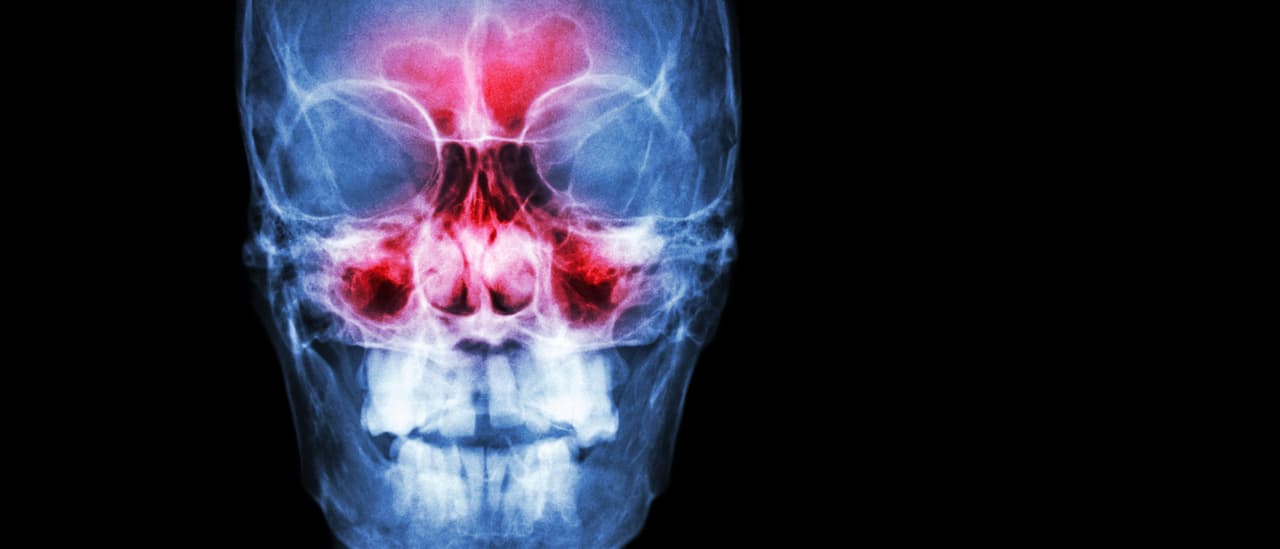

Según el otorrinolaringólogo Ricardo Landini Lutaif Dolci, de la Clínica Dolci, la sinusitis es una inflamación que afecta a los senos paranasales, que son cavidades del rostro que tienen relación con la mucosa de la nariz. El problema puede ser causado por alergias, como rinitis alérgica, contaminación del aire o infecciones, como gripes y resfriados.

En raros casos, la sinusitis puede convertirse en meningitis, que es una inflamación aguda de las membranas que recubren la médula espinal y el cerebro.